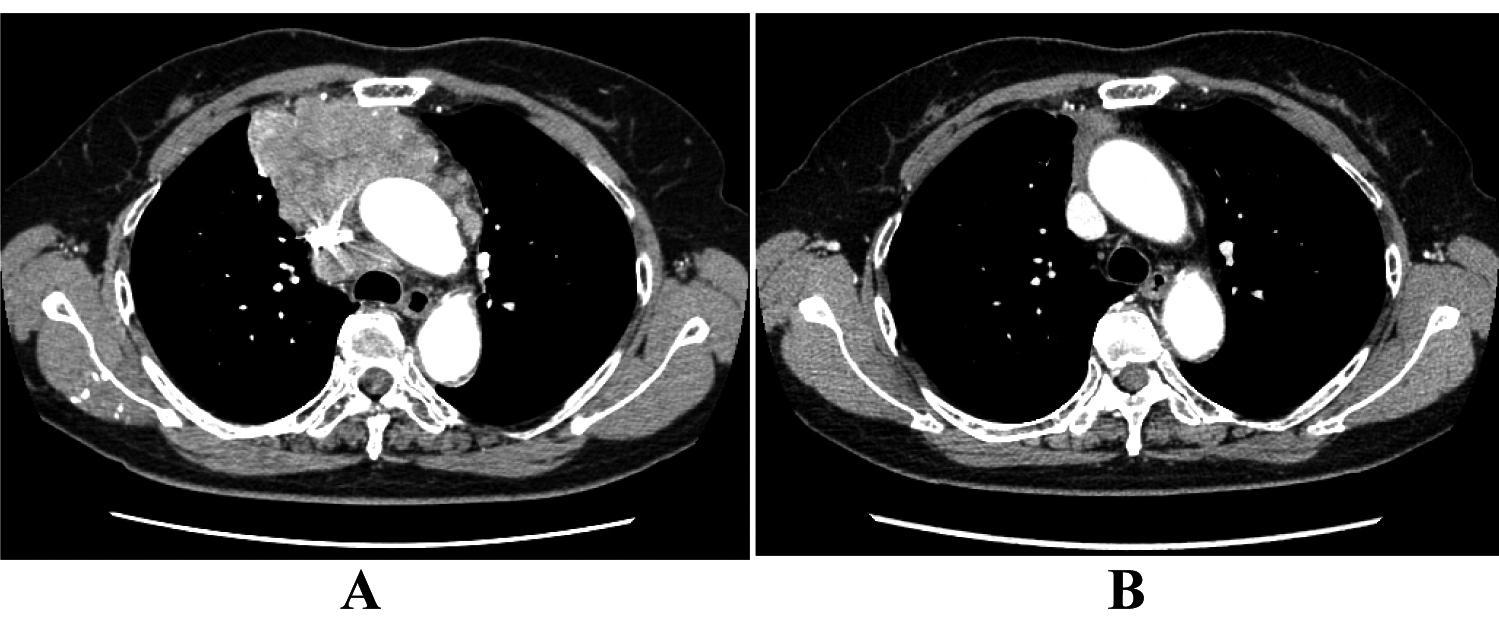

A 70-year-old woman was referred to our hospital in October 2007 because of chest discomfort and anterior mediastinal mass on chest computed tomography (CT) (Fig. 1A). Percutaneous CT-guided biopsy was performed and the lesions were confirmed histologically to be epidermoid-type thymic carcinoma. She was treated with 4 cycles of a combination of cisplatin (50 mg/m2) and doxorubicin (40 mg/m2) on day 1, vincristine (0.6 mg/m2) on day 3, and cyclophosphamide (700 mg/m2) on day 4 (ADOC chemotherapy), and showed partial response to the treatment (Fig. 1B). Subsequently, the residual tumor was surgically resected in March 2008, followed by a total of 60 Gy (2 Gy × 30 days) thoracic radiotherapy. In October 2009, positron emission tomography (PET) and chest CT scan revealed right clavicular lymph node swelling (Fig. 2A). Although biopsy was not performed, this was considered relapsed thymic cancer. She was retreated with modified ADOC chemotherapy using nedaplatin (80 mg/m2) instead of cisplatin because of her reduced renal function (creatinine clearance < 50 ml/min). After 4 cycles of modified ADOC, the patient showed a complete response (Fig. 2B). As of October 2011, the patient is still alive without any symptoms or further recurrence.

![]() Click for large image | Figure 1. The response to initial ADOC chemotherapy in case 1. Chest computed tomography before initial ADOC chemotherapy (A) and after four cycles of initial ADOC chemotherapy (B). |